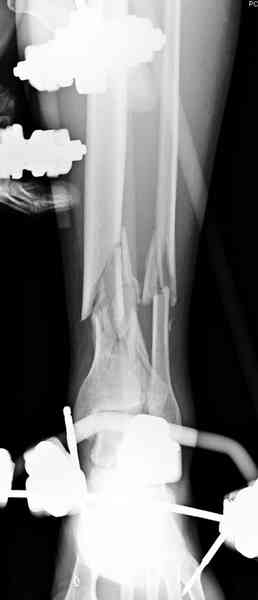

Предыдущей сменой до 4:00 утра по поводу открытого перелома бедра, тибиал плато, пилон и надколенника сделана операция.

На голень наружный фиксатор, рану на бедре ушили (рана была изнутри кнаружи всего 2 см). По протоколу травматических больных, до операции обследован ангиографически, (у больного дистально не смогли определить пульсацию) сосудистый хирург подтвердил проходимость на всем протяжении магистрального сосуда нижней конечности по снимкам ангиограмм.

Срочная фасциотомия на всех 4 компартментах: латерально и медиально,

на бедре измерения не подтвердили подозрения на компартмент синдром и рана была закрыта вакуумной губкой (wound VAC).

В настоящее время больной в реанимации по поводу Черепно Мозговой Травмы и состояние улучшается. Запланировал ушивание раны в пятницу, если позволит состояние мягких тканей и при отсутстви отека возможно удастся просунуть перкутанномедиальную пластину.